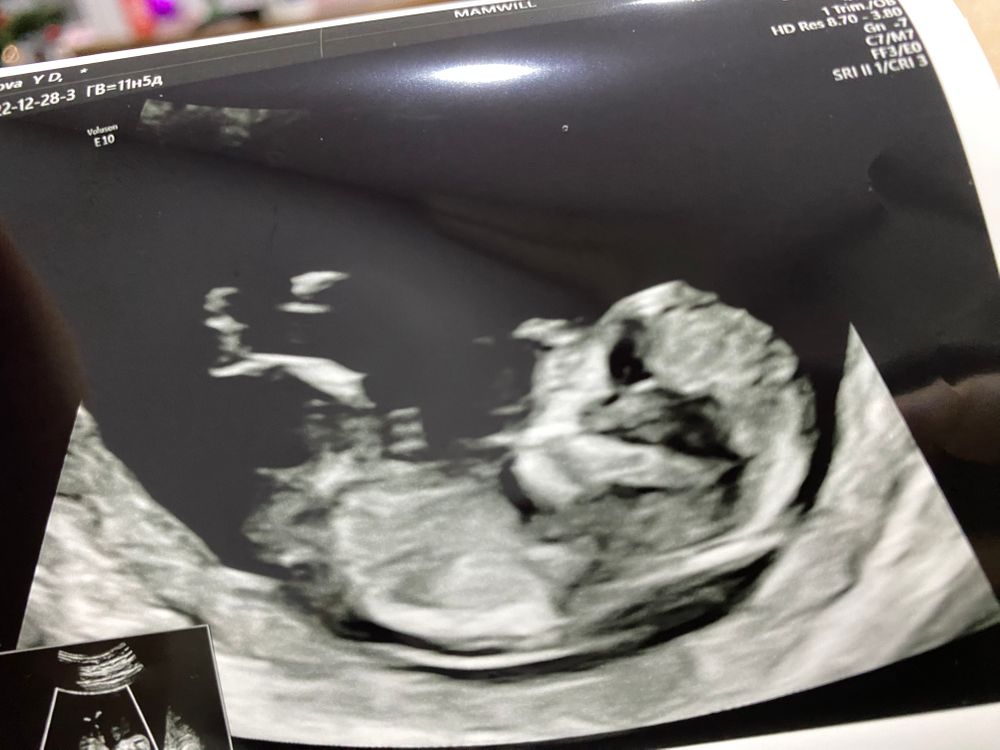

Скрининг 1

Замечательный малышок! Пусть и дальше растет и все будет хорошо!!!

Nysha, я когда пришла, видно волновалась и он такие пируэты выдавал, не сфоткать, а когда я успокоилась - уснул, да еще и рукой лицо закрыл, понятно что фотка неудачная будет) врач даже просила встать походить, еще раз посмотрели, а он все равно вот как застыл в таком положении 😁